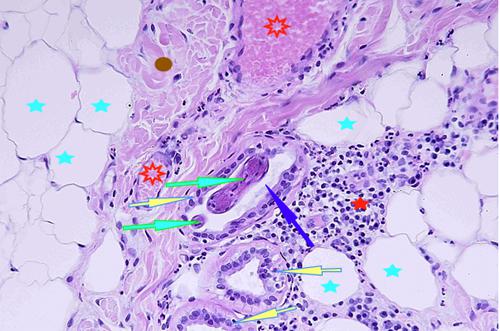

Photo 25 (Hémalun Eosine X 400) peau velue : Vue rapprochée de la Photo 24 montrant

un élément vermiforme dans la lumière d’une glande sudorale apocrine épitrichiale,

en coupe longitudinale tangentielle. On note un infiltrat inflammatoire

périsudoral riche en plasmocytes et en éosinophiles.

Légendes de la Photo 25 :

- Étoile rouge vides : vaisseau sanguin (lumière d’un) et granulocytes éosinophiles (infiltrat inflammatoire dermique périsudoral)

- Étoiles vertes : infiltrat inflammatoire dermique périsudoral, plasmocytes

- Rond marron : collagène

- Étoile turquoise : adipocyte

- Flèche jaune : glande sudorale apocrine épitrichiale

- Flèche bleue : lumière de la glande sudorale

- Flèche verte : cuticule du ver rond

- Flèche violette : cellules musculaires du ver rond